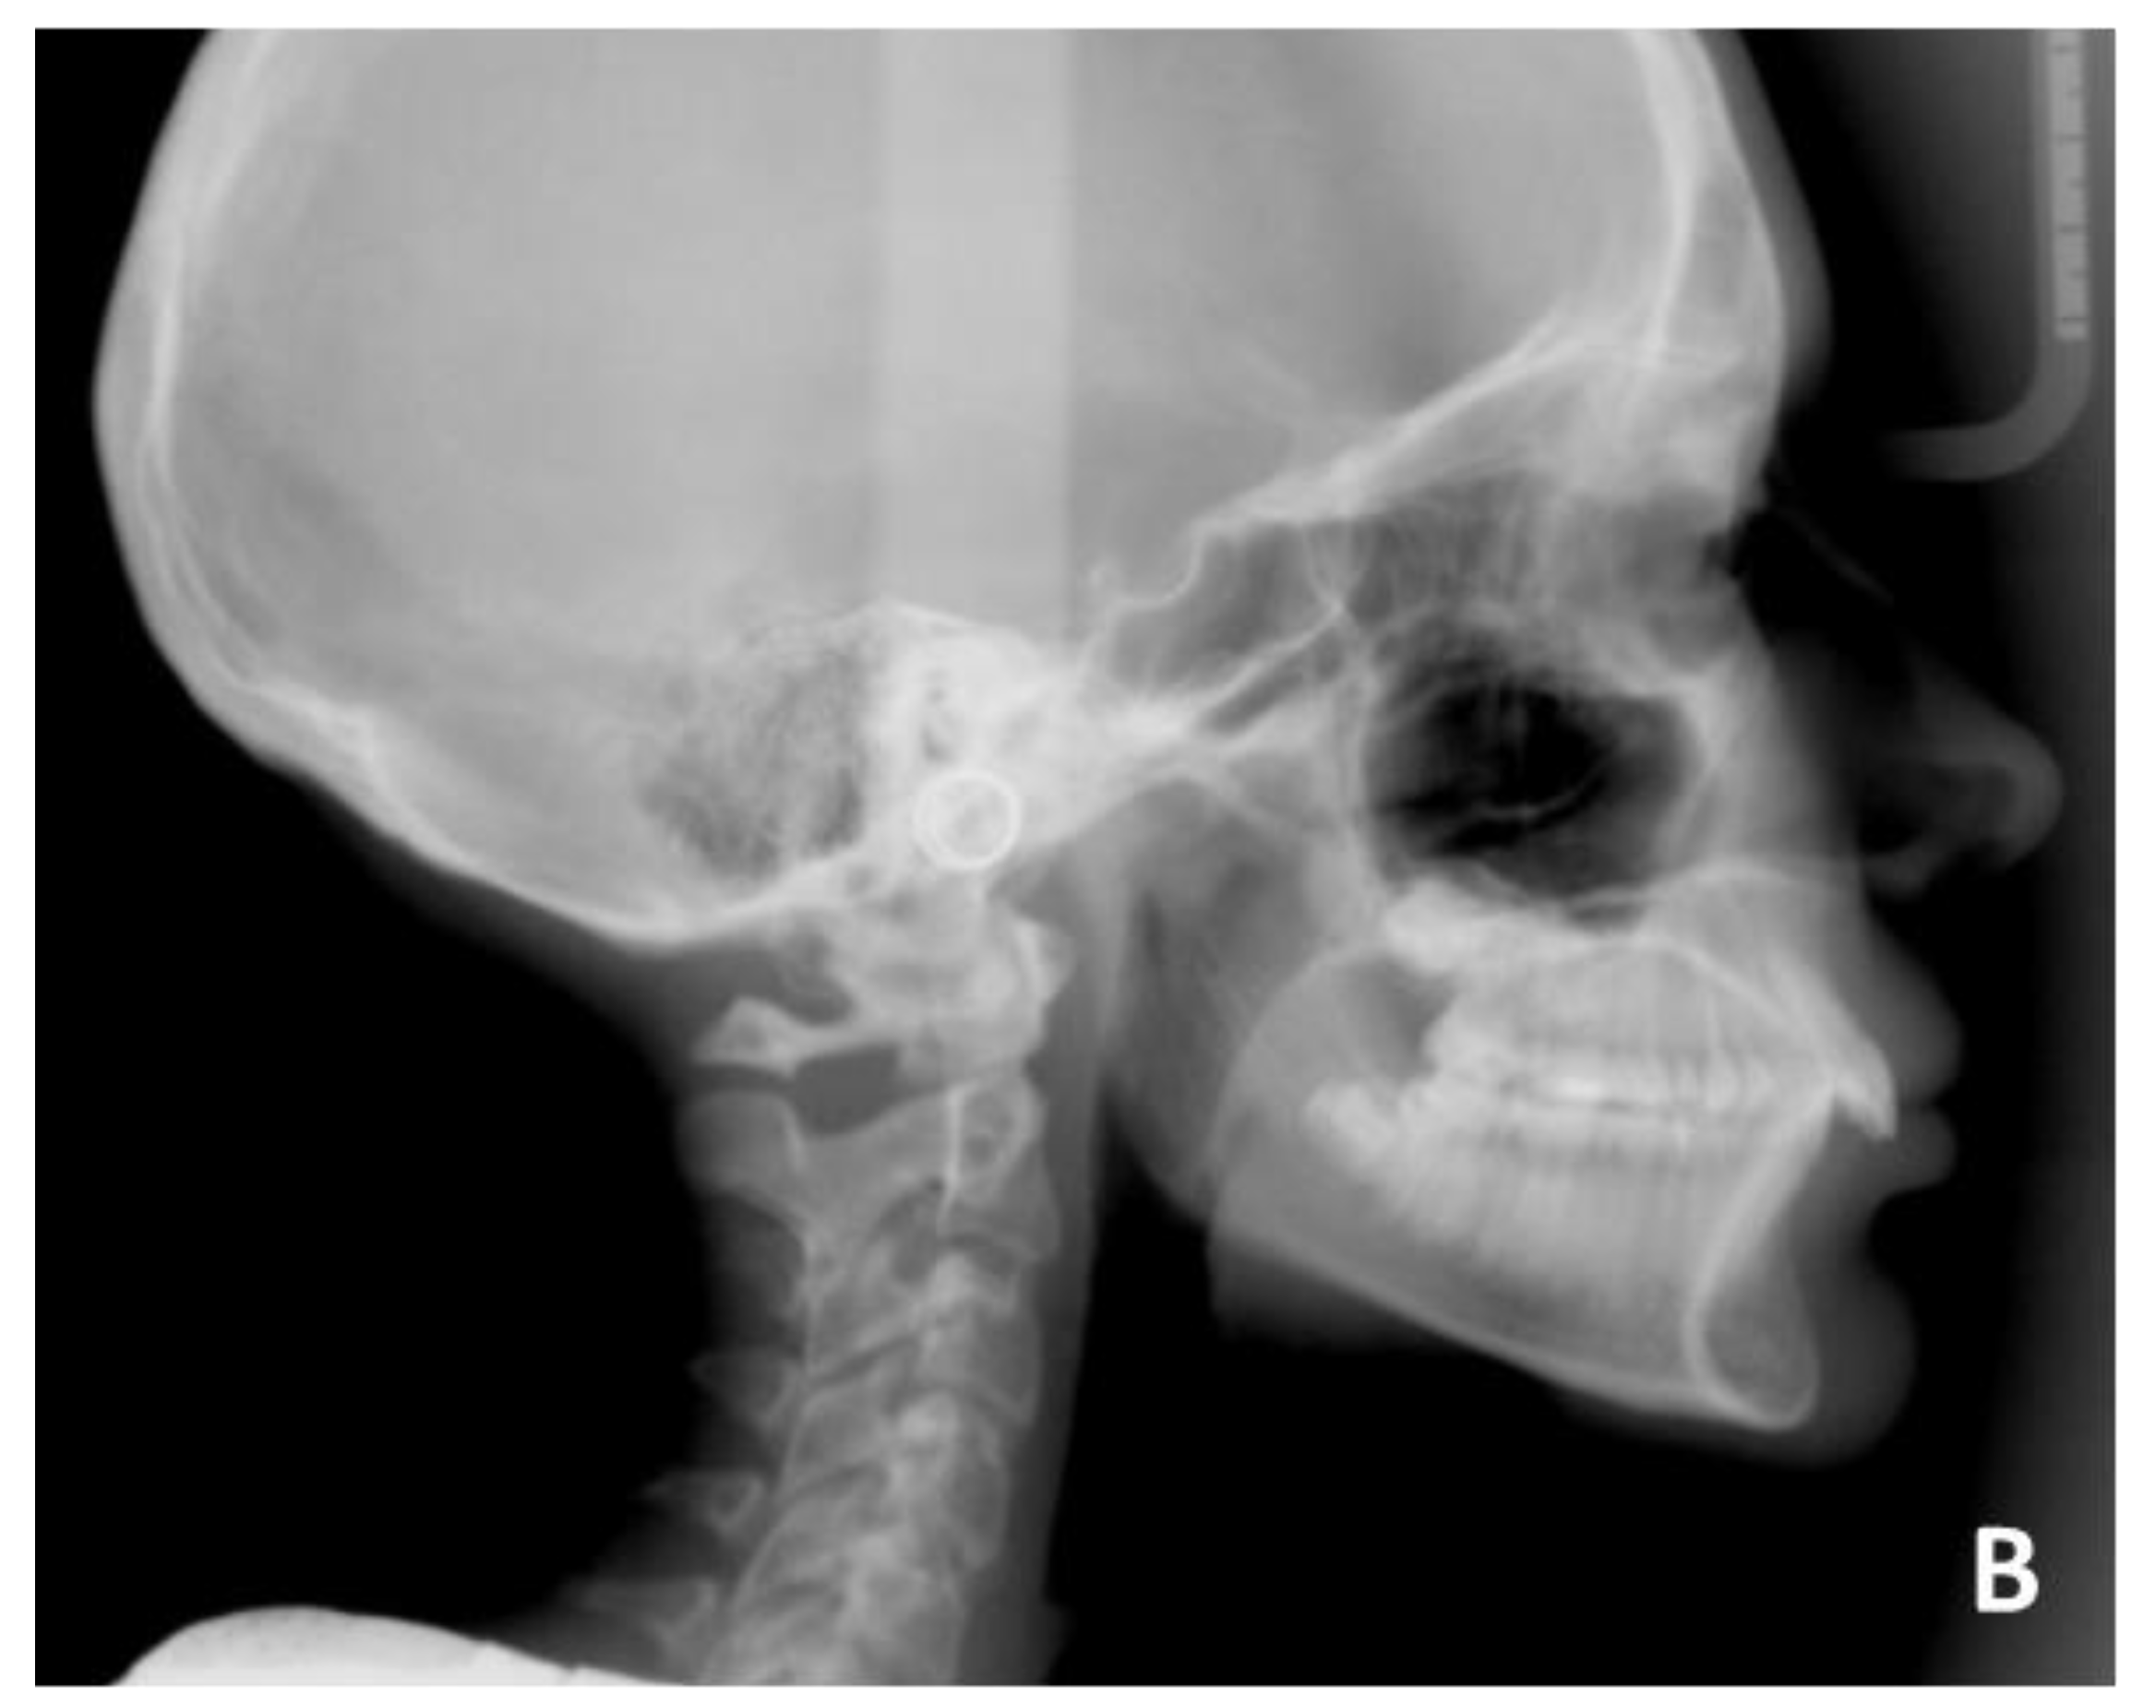

3. Case Report Number 1

The first case reported was an adult male patient who had already undergone orthodontic treatment in the past with the extraction of the four first premolars. The orthodontic situation (Figure 9, Figure 10 and Figure 11 and Table 1) showed a dentoskeletal class II malocclusion, upper and lower crowding, severe deep bite with impingement of the lower incisors on the palate, retroclination of the upper and lower incisors, and convex and biretruded profile. The patient was strongly brachyfacial, and therefore, a deep bite was not only dental but also skeletal. The patient showed good exposure of the upper incisors; therefore, in the resolution of the deep bite, it was preferable not to intrude upper incisors in order not to worsen the patient’s aesthetics.

The treatment was conducted exclusively with clear aligners and followed the protocol for the resolution of the deep bite that was described above. It lasted approximately 18 months, with only one little refinement. At the end of the treatment, the resolution of the deep bite and an important leveling of the patient’s curve of Spee was clearly evident, as can be seen in the comparison between the initial and final orthopantomography.

The exposure of the lower incisors at the end of the treatment was normal, the upper and lower crowding was resolved, and the dental class was corrected. In fact, at the end of the treatment, the patient was in molar and canine class I. Cephalometric analysis (Table 2) showed skeletal deep bite, skeletal class II, and better inclination of upper and lower incisors. At the end of the treatment, intra- and extra-oral photos of the patient and X-rays were taken (Figure 12 and Figure 13) and, after few days, a removable Essix for long-term retention was delivered. Final cephalometric tracing is showed in Figure 14.

Figure 10. Pre-treatment radiographic of case number 1: (A) orthopantomography; (B) lateral cephalogram.